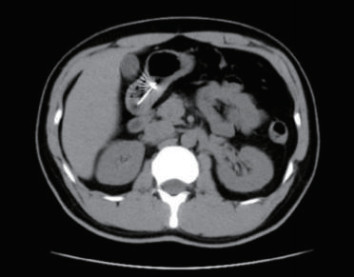

1 一般资料患者,男性,32岁,职员,因“误吞金属钉状物7 d”就诊。患者7 d前误吞入金属钉状物一根(大小约3 cm),患者无明显不适症状,未诊治。4 d前出现下腹隐痛,行急诊全腹CT检查,见图 1,行急诊胃镜检查未见明显异物。后复查腹部CT示异物进入小肠内(图 2),普外科会诊建议随访。2 d前复查腹部CT(图 3),继续保守治疗。1 d前患者为行异物取出入院,复查腹部CT可见异物至结肠内(图 4)。急诊予以聚乙二醇电解质散导泻清肠,行无痛肠镜下异物取出术。本文已通过本院伦理委员会审批,伦理审批号为:(2021)伦审研第(0252)号,并通过免除知情同意申请。完善术前检查,进行药物导泻清肠时,关注患者有无腹痛等现象,以免因服用药物清肠,肠蠕动加快,尖锐异物在消化道内随蠕动前行,尖端嵌插在肠壁中而停滞不前,并随着后方内容物的推进,加深尖锐异物刺入肠壁,最终导致穿孔及出血的发生。本例患者安置在独立单人间进行肠道准备,不定时进行腹部查体及观察排泄物的性状,早期发现穿孔、出血指征,以便尽早进行外科手术干预。与此同时,内镜中心医护人员联合外科、放射科、麻醉科医生制定诊疗方案,若发生此类情况,立即予急诊行腹部X线或CT检查,一旦确定出现穿孔或出血等情况,即刻行急诊手术治疗。

| 图 1 腹部CT示胃窦幽门部尖锐异物 |